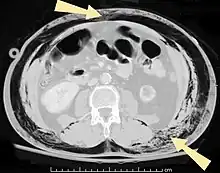

O enfisema pode produzir protuberâncias, como nódulos móveis com ruídos crepitantes a palpação. Em uma radiografia de tórax, o enfisema subcutâneo pode ser visto como estriações radioluzentes (escuras) nas áreas com músculos. O ar nos tecidos subcutâneos pode interferir na radiografia do tórax, potencialmente obscurecendo condições graves, como o pneumotórax. Também pode reduzir a eficácia do ultrassom.[8] Também é visível na tomografia e na ressonância magnética como bolhas escuras.